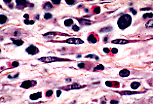

| 网状细胞为星芒状细胞,其突起与相邻网状细胞的突起相互连接,形成广泛的网络结构。该细胞网络外覆纤维网络(由 III型胶原构成的网状纤维 组成),但在本标本中不可见。 | |